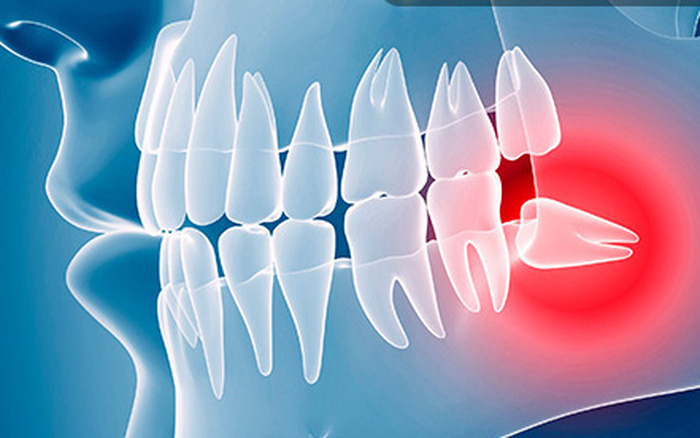

- Răng khôn mọc lệch viêm sưng nướu.

- Răng khôn mọc sâu bên trong gây tích tụ thức ăn, khó khăn trong việc vệ sinh răng miệng gây sâu răng và hôi miệng.

- Răng khôn mọc lệch gây vỡ, sứt, lung lay, thậm chí mất răng số 7.

- Những bất thường của răng khôn nếu không được chữa trị kịp thời có thể gây nhiễm trùng và hỏng tủy răng